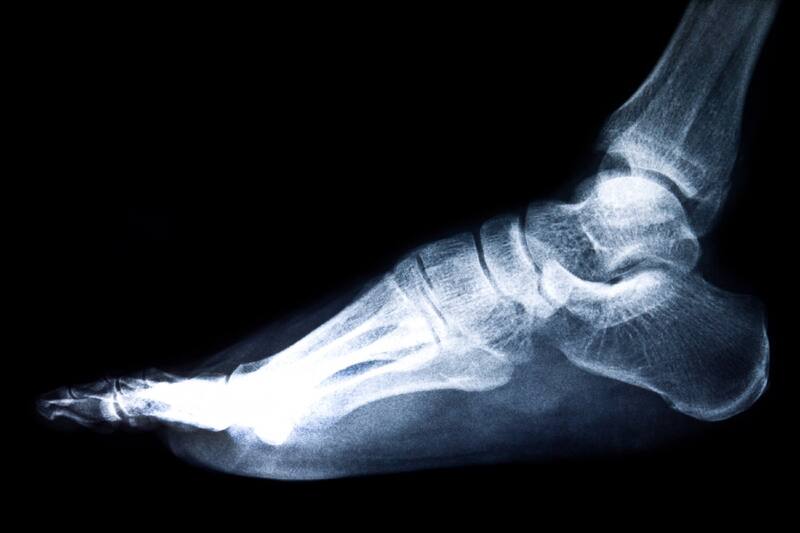

Son más de 90 las coberturas por PAD, una de ellas es la Osteosíntesis, que consiste en la cirugía que repara diversas fracturas en diferentes partes del cuerpo y acá te enumeramos algunas de ellas para que puedas recibir atención oportuna.

Las Osteosíntesis que cubre Fonasa con Pago Asociado a Diagnóstico (PAD) son:

Osteosíntesis Tibio-Peroné

La Osteosíntesis Tibio-Peroné es la intervención quirúrgica de fracturas de la tibia y el peroné (pierna) mediante la implantación de diferentes dispositivos como placas, clavos, tornillos, alambre y agujas para reducir y fijar de forma permanente este sector anatómico.

El PAD cubre el tratamiento quirúrgico de la fractura de la tibia o el peroné (pierna) por Osteosíntesis en cualquier técnica, honorarios médicos, insumos utilizados, post operatorio, controles integrales, tratamiento y exámenes.